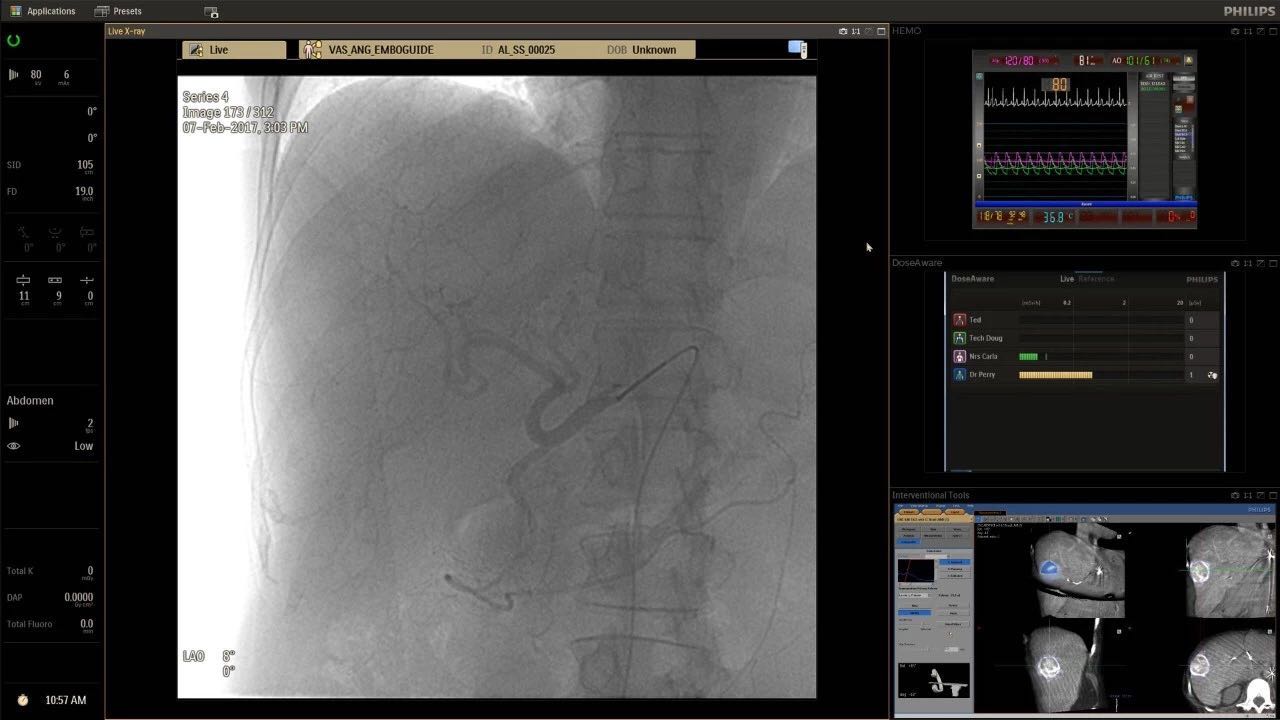

在日益復雜的干預期間,臨床醫(yī)生需要快速、輕松地可視化關鍵解剖結構并確定手術過程中患者的變化。2019年1月17日,飛利浦宣布推出采用FlexArm的Azurion 7 C20,旨在提高圖像引導程序的定位靈活性。

帶有FlexArm的Azurion 7 C20 包含一系列創(chuàng)新技術,使臨床醫(yī)生可以更輕松地在整個患者身上進行二維和三維成像。當臨床醫(yī)生移動系統(tǒng)時,圖像光束自動保持與患者的對準,允許更一致的可視化并使他們能夠將注意力集中在治療上。

(FlexArm C型臂可以沿著工作臺的兩側提供偏心成像。這允許醫(yī)生在左臂或右臂上進行徑向進入病例,完全或部分伸展,而無需移動患者或樞轉桌子。X射線束與手臂保持對齊,以促進其整個長度的平滑導航,而無需進行持續(xù)調整。)

飛利浦表示,采用FlexArm設計的Azurion 7 C20可提供卓越的靈活性和直觀的控制。該系統(tǒng)由智能運動引擎驅動,可在八個不同的軸上移動,所有這些軸均由其單個“Axsys”控制器控制。臨床醫(yī)生的模擬測試表明,該系統(tǒng)有可能顯著減少患者,工作人員和設備的重新定位,從而改善微創(chuàng)手術的可及性,包括通過患者手腕進入身體的手術(橈動脈入路),并降低患者的風險。無意中拔出電線和管子,以及節(jié)省大量時間。該系統(tǒng)非常適合混合手術室(OR),可滿足一個房間內的多種專業(yè)需求,例如手術和血管內手術的組合。

FlexArm在不少于8軸的情況下旋轉,從而創(chuàng)建幾乎無限的靈活性來執(zhí)行成像,從頭部到腳部在左側和右側進行2D和3D可視化。圖像光束保持與患者對齊,允許在旋轉或角度期間更好地可視化解剖結構。使用Axsys運動控制系統(tǒng)輕松操作支架。